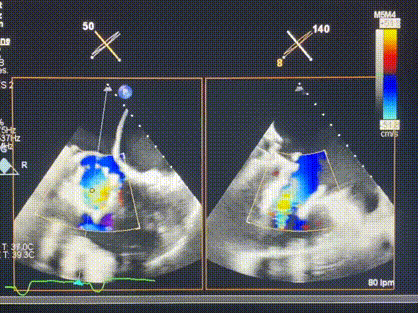

術(shù)后超聲顯示僅殘余微量瓣周漏

LuX-Valve Plus經(jīng)血管三尖瓣置換系統(tǒng)此次“出海”圓滿完成,術(shù)后Rodrigo Estévez-Loureiro教授對LuX-Valve Plus經(jīng)血管三尖瓣置換系統(tǒng)的器械性能和治療效果大為稱贊,認為LuX-Valve Plus的手術(shù)體驗非常好。術(shù)后即刻超聲顯示三尖瓣反流幾乎完全消失,血流動力學(xué)改善顯著,患者恢復(fù)快。在面對復(fù)雜解剖結(jié)構(gòu)、超聲影像質(zhì)量不佳、有起搏導(dǎo)線干擾時,Lux-Valve Plus也體現(xiàn)了極強的適應(yīng)性。Thomas Modine教授和Anson Cheung教授也肯定了LuX-Valve Plus術(shù)中操作的便捷性,認為LuX-Valve Plus容錯率高,對術(shù)中影像的依賴較小,后期希望可以更多的應(yīng)用LuX-Valve Plus三尖瓣置換系統(tǒng)于臨床實踐,讓更多的三尖瓣重度反流患者盡早獲益,改善預(yù)后。